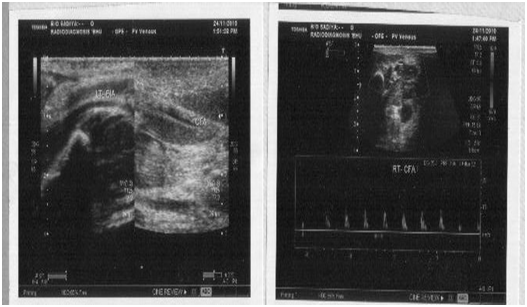

His hemogram revealed Hb: 10.8 gm/dl, TLC:15,000/mm3, DLC: N76,L20,E3,M1 and Platelet: 140,000/mm3. His renal and liver function tests were normal. There was no evidence of hemolysis in peripheral smear with reticulocyte count less than 0.5% and negative coomb’s test. His c-reactive protein was 0.91 mg/L (non-significant) and aerobic blood culture was sterile. Prothrombin and activated partial thromboplastin time were normal. Test for anti-cardiolipin antibodies [IgG:6 GPLU/mL(N:<10), IgM MPLU/mL(N:<10) and anti-thrombin III:24.4mg/dL (normal range:19-39 mg/dL) were negative. Serum protein-C was 77.8% of normal (deficiency<if less than 60%) and protein-S: 91.7% (deficiency<if less than 70%) was within normal limit. Factor V mutation analysis revealed no abnormality. Colour Doppler study of lower limb showed uncompressible common iliac vein with echogenic lumen and no evidence of flow, suggestive of left common iliac vein thrombosis, extending up to superficial femoral vein (Figure 2).